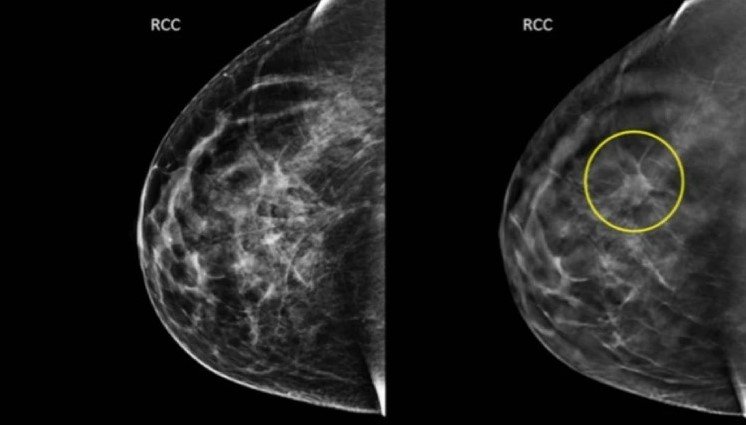

🎗️ Mamas densas: um desafio crescente no rastreamento

O termo mamas densas é um dos que mais geram dúvida nos laudos. Muitas mulheres pesquisam: mama densa é perigoso, mamas densas aumentam risco, quem tem mama densa precisa de ultrassom?

A densidade mamária se refere à proporção entre tecido fibroglandular e gordura. Quando a mama tem mais tecido fibroglandular, a leitura da mamografia pode ficar mais difícil, porque tanto esse tecido quanto algumas lesões aparecem claros na imagem.

🧠 Analogia prática

Imagine tentar enxergar uma nuvem branca atrás de uma parede branca.

Esse é o desafio da mamografia em mamas densas.